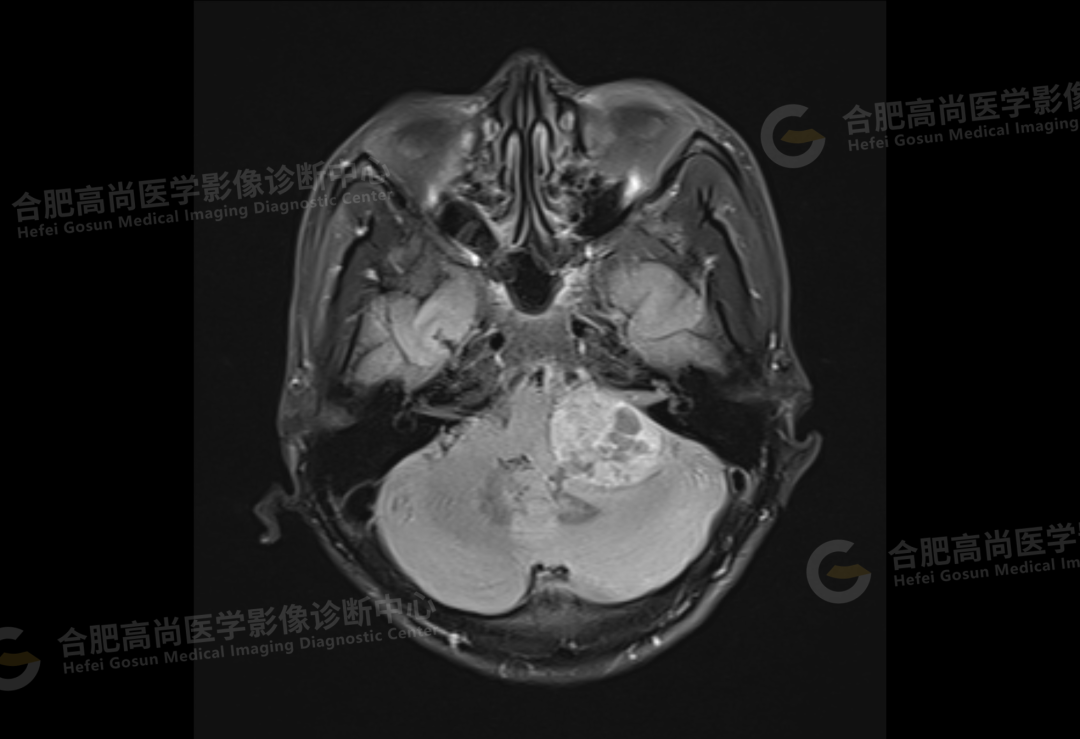

2、颅脑 MRI

颅脑 MRI 平扫+增强显示:左侧桥小脑角区可见类圆形囊实性异常信号,呈长 T1 长 T2 信号,flair 序列呈混杂高信号,内可见坏死囊变,大小约 3.0*3.5 cm,边界清晰,增强后病灶实性成分明显强化,囊变区未见明显强化,左侧内听道扩大,听神经增粗伴明显强化,病灶邻近小脑及桥脑受压推移变形,四脑室变形变窄,对侧桥小脑角区未见异常。

结论:左侧桥小脑角区占位,考虑听神经瘤。